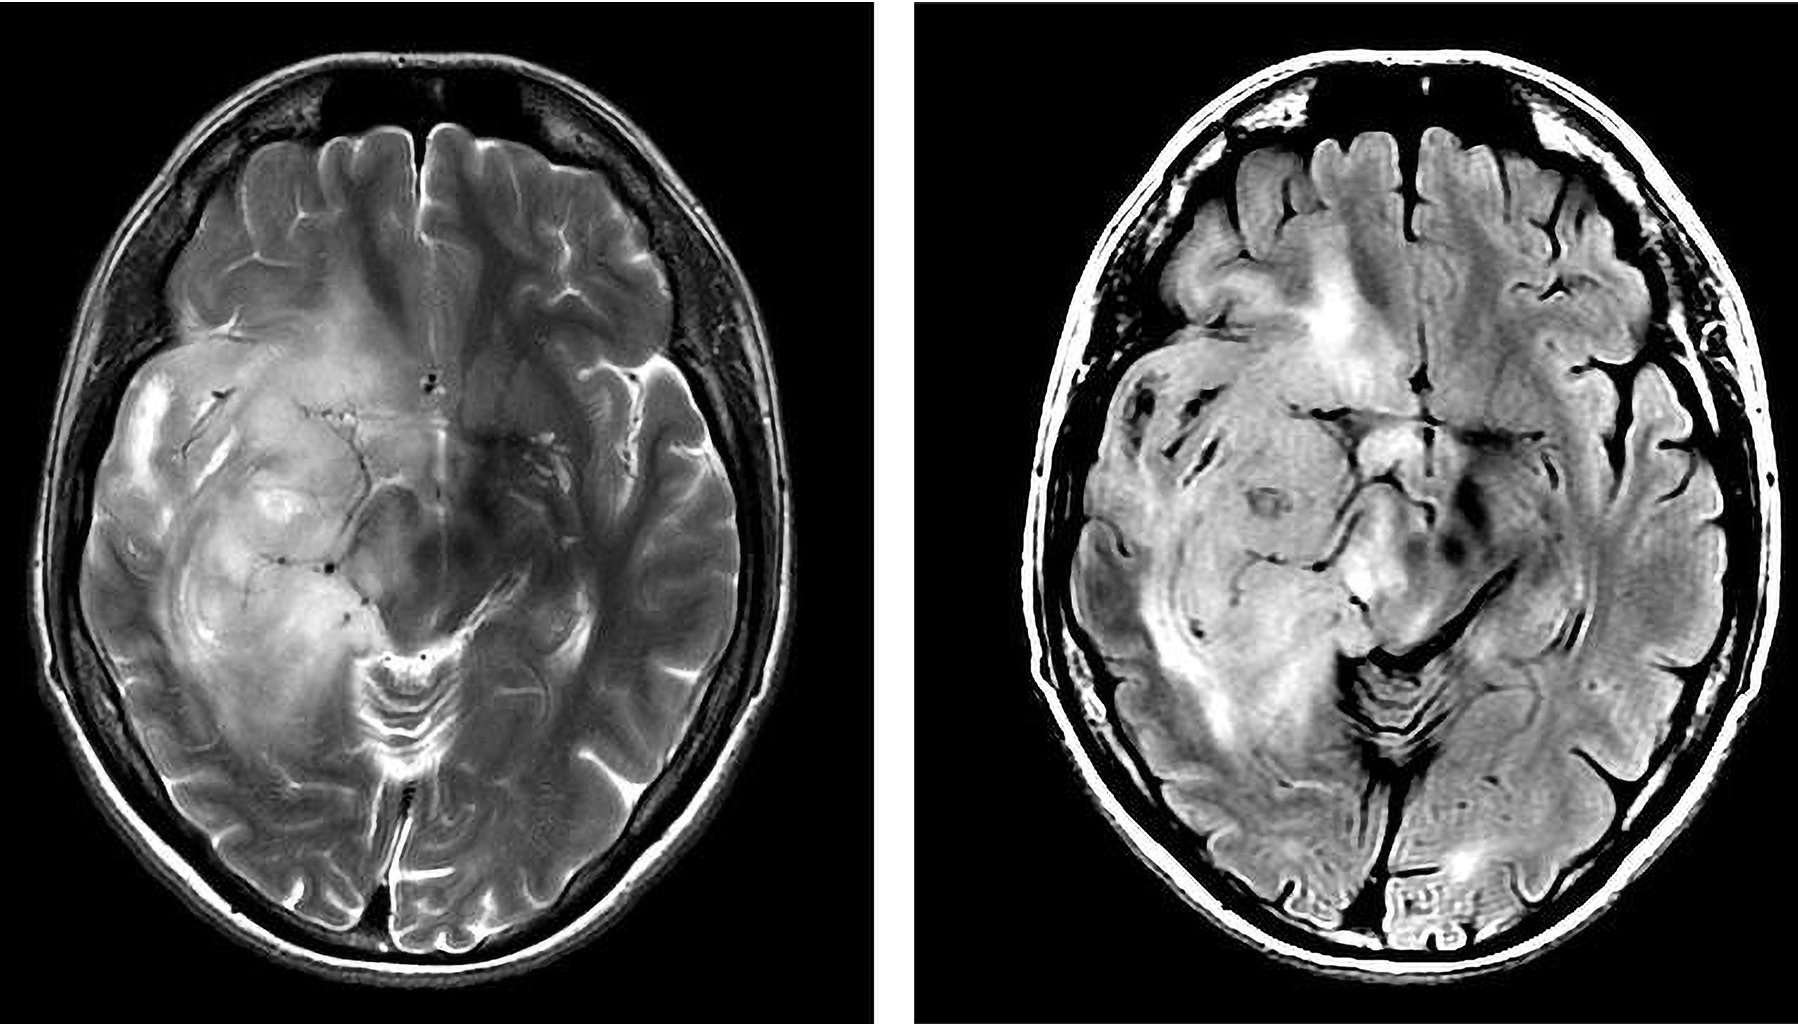

По данным T2–ВИ, T2-FLAIR определяли сигнальные характеристики диффузно-растущего объемного образования и выбирали зону интереса, на которую впоследствии выставлялся воксел для получения спектральных характеристик в зоне патологических изменений (рис. 1).

Рис. 1. МР-изображения диффузно-растущей глиомы правой лобно-височной области. В Т2-ВИ и Т2 Flair опухоль имеет гиперинтенсивный сигнал и нечеткие контуры.

Fig. 1. MR images of a diffuse glioma in the right frontotemporal region. In T2 and T2 Flair, the tumor has a hyperintense signal and fuzzy contours.